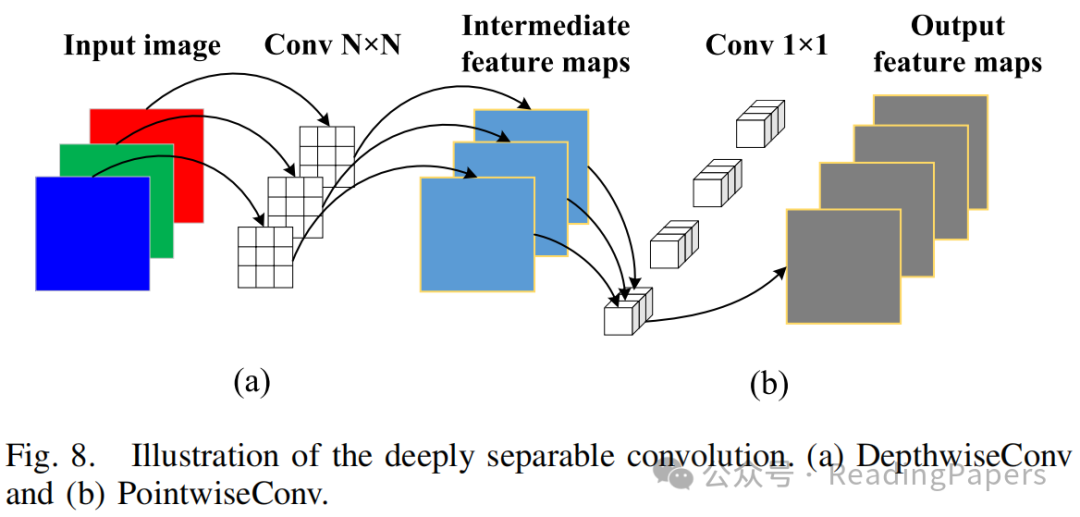

E. 解码器

为了增强有效感受野并使其更容易混合远距离上下文信息,融合后的特征图被输入到最深层的下采样层的Res-Conv块中。如图2所示,Res-Conv块由层(本文中设置为7)组成,通过深度卷积(即核大小)和点卷积(即核大小)混合空间位置和通道位置,进一步获取上下文依赖关系。此外,深度卷积中的组通道数等于输入特征图的通道数,并且每个卷积操作都应用了高斯误差线性单元(GeLU)激活和批归一化,如下所示:

其中,表示Res-Conv块中第层的输出特征图,表示GeLU激活,表示批归一化。和表示深度可分离卷积的两个主要阶段,其网络架构如图8所示。

在阶段(图8的(a)部分),每个卷积核被指定处理输入图像的单个通道,生成与输入通道数匹配的中间特征图。例如,当处理的彩色图像时,该过程生成三个大小为的中间特征图。然而,这种每个通道独立进行卷积的方法未能充分利用通道间特征相关性。因此,它忽略了同一空间位置上通道之间的有价值信息交互。为了解决这一局限性并获得最终输出特征图,阶段(图8的(b)部分)是一个关键操作。在这里,使用大小为的卷积核,其中表示前一层特征图的通道数。通过过程,每个卷积核沿通道维度组合中间特征图,有效地生成新的特征图。该方法显著减少了参数数量和计算复杂度,同时保持了令人满意的网络性能。

最后,作者采用双线性插值方法对特征图进行上采样。解码器由四个阶段组成,每个阶段包括一个典型的卷积块、一个上采样操作和ReLU激活函数。解码器首先接收低分辨率()的融合特征图,经过四次连续的上采样操作后生成高分辨率()的特征图。然后,重建的特征图通过分割头中的卷积生成最终的分割结果,其中通道数与预测类别数相同。